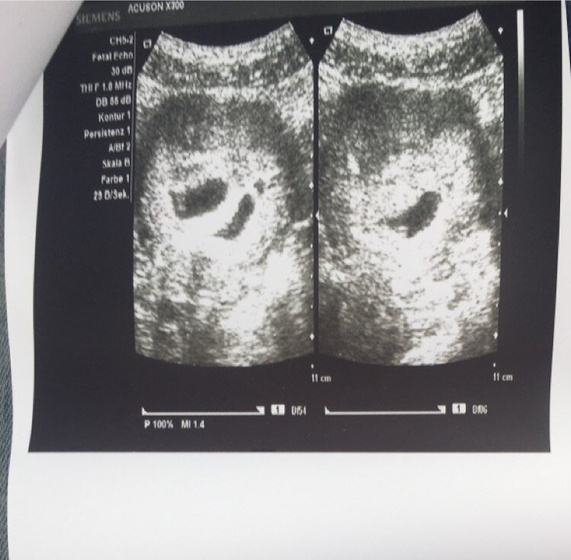

Поехала на узи, там мне подтвердили многоплодную беременность!!!!!!!❤️

У обоих сердечко уже стучит, включали мне оба послушать… ох я наревелась от счастья)))??

Но… нашли на том, что поменьше отслойку совсем небольшую...(((Меня на учёт должны поставить только 20числа, через 10 дней… до этого числа и талонов нет даже попасть(((Как быть?